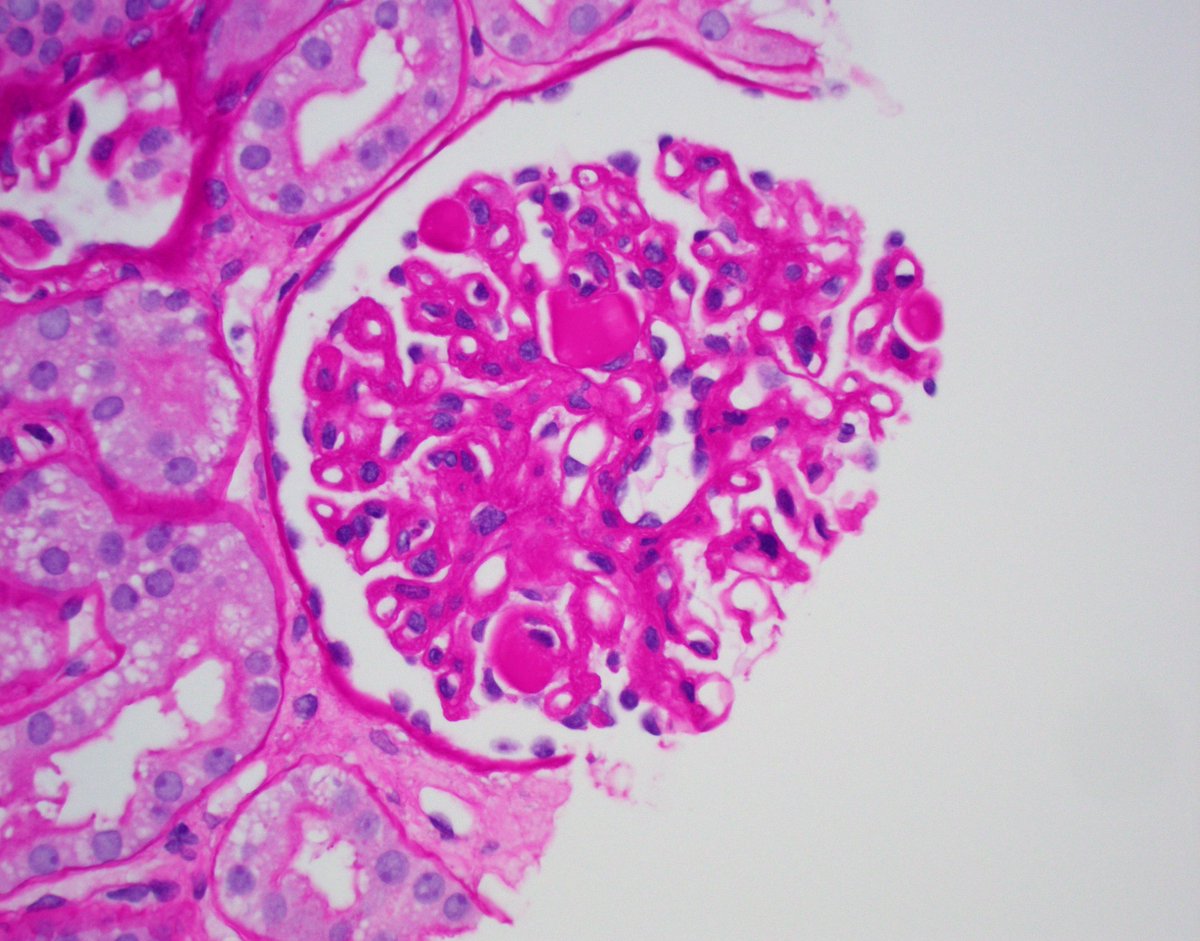

Bx for new onset NS in an older adult. Serologic work up including SPEP/UPEP IFE negative. Bx shows membranous pattern with few double contours. IgG3-k restriction and mottle EM deposits c/w PGNMID with membranous predominant pattern. PLA2R- #renalpath #pathtwitter #nephrology